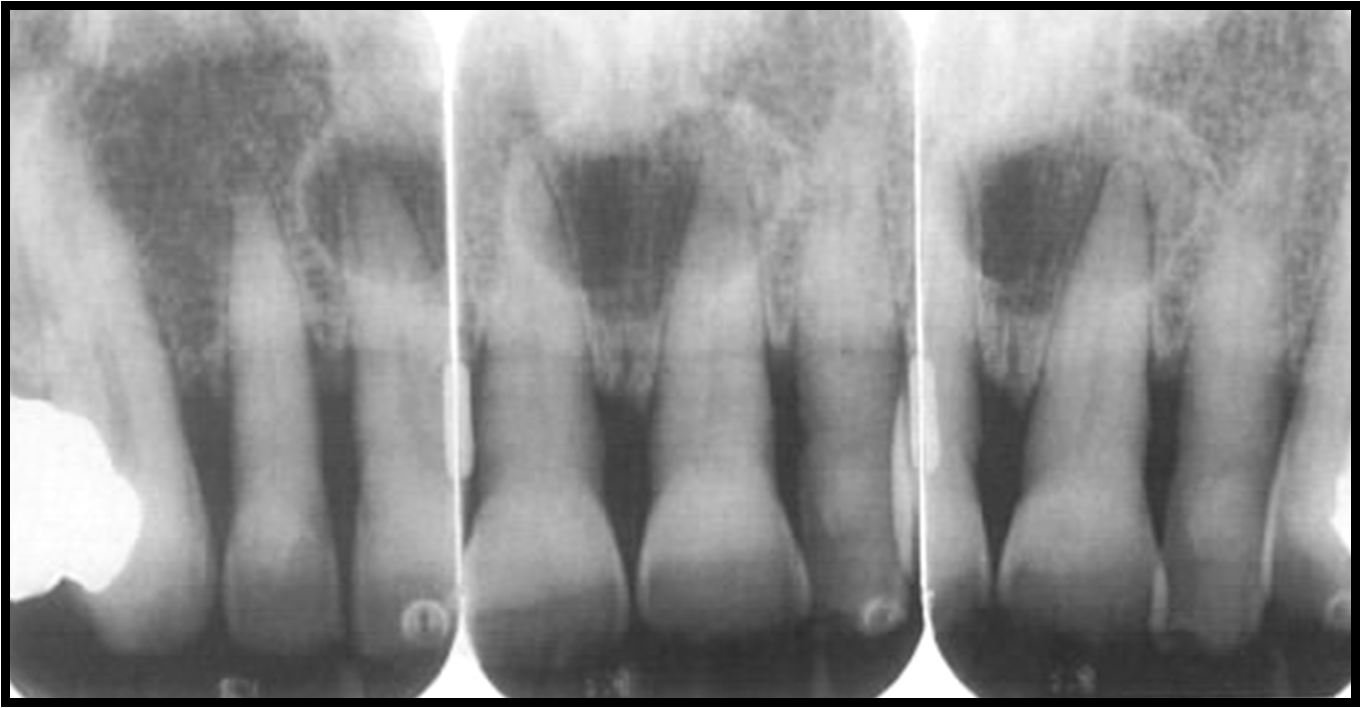

Radiographic Appearance of Cysts Part 3 and Scintigraphy Intelligent Dental Cyst Dangerous if you have a permanent tooth that's coming in and a clear sack of fluid has formed around it, you may have what's called a dentigerous cyst. people who are of the age group 20 to 30 years are affected by the dentigerous cyst. Learn about the symptoms, treatment & prevention of. Cysts and granulomas are dangerous because. Dental Cyst Dangerous.